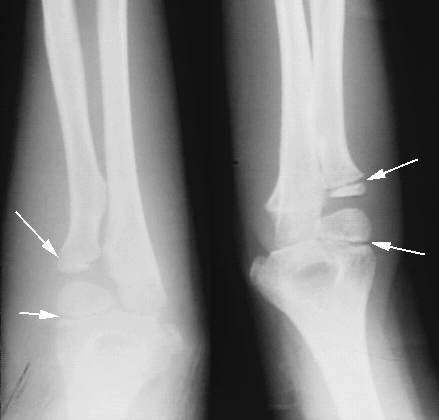

Upper Limbs: Elbow Growth Plates:

Arrows: Radial & Humeral Growth Plates.